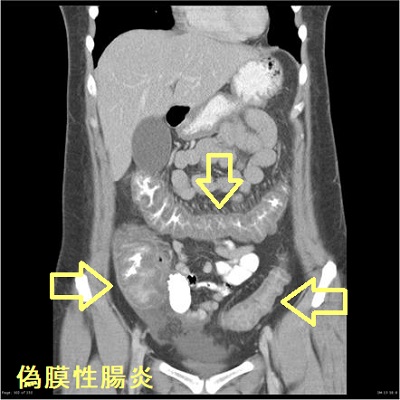

偽膜性大腸炎の原因となる抗生剤は

- かつてはリンコマイシン(Lincomycin)やクリンダマイシン(Clindamycin)

- 最近は、使用頻度の高いセファロスポリン系抗生物質が多い

抗生剤投与中、投与中止後1-2週間後~2カ月以内に発熱、腹痛、下痢で発症します。

すべてが偽膜性大腸炎にならず、非特異的結腸炎のこともあります。重症例では腸穿孔・中毒性巨大結腸をおこし、甲状腺外科から消化器外科へ転院になります。

偽膜性大腸炎の画像所見は、直腸から連続的に大腸、更には小腸まで病変が及び、

- CTでは壁肥厚が著明;症状の割に重篤(重症)感がある

- 大腸ファイバーでは偽膜形成

偽膜性大腸炎の確定診断は、糞便検査で

- Clostridium difficile トキシン陽性

- Clostridium difficile を検出

偽膜性大腸炎の治療は、

- 原因となった抗生物質中止

- バンコマイシン散剤内服(静脈用ではない)・メトロニダゾール(フラジール®;アメーバなどの寄生虫,ピロリ菌除菌薬)に切り替える

Clostridium difficile は芽胞を形成するためアルコール消毒で完全に除菌できず、アルデヒド(グルタラール,フタラール)、過酢酸、次亜塩素酸を使用せねばなりません。芽胞は環境中に長期間存在するため、医療従事者には徹底した接触予防が求められます。芽胞を拡散しない様、流水と石鹸で手洗いが必要。

甲状腺機能低下症による粘液水腫巨大結腸に、Clostridium difficile が起因菌の偽膜性大腸炎を合併した報告があります(Mayo Clin Proc. 1992 Apr;67(4):369-72.)。

Clostridium difficile が起因菌の偽膜性大腸炎で、亜急性甲状腺炎を発症した報告があります(BMJ Case Rep. 2018 Dec 18;11(1):e226711.)